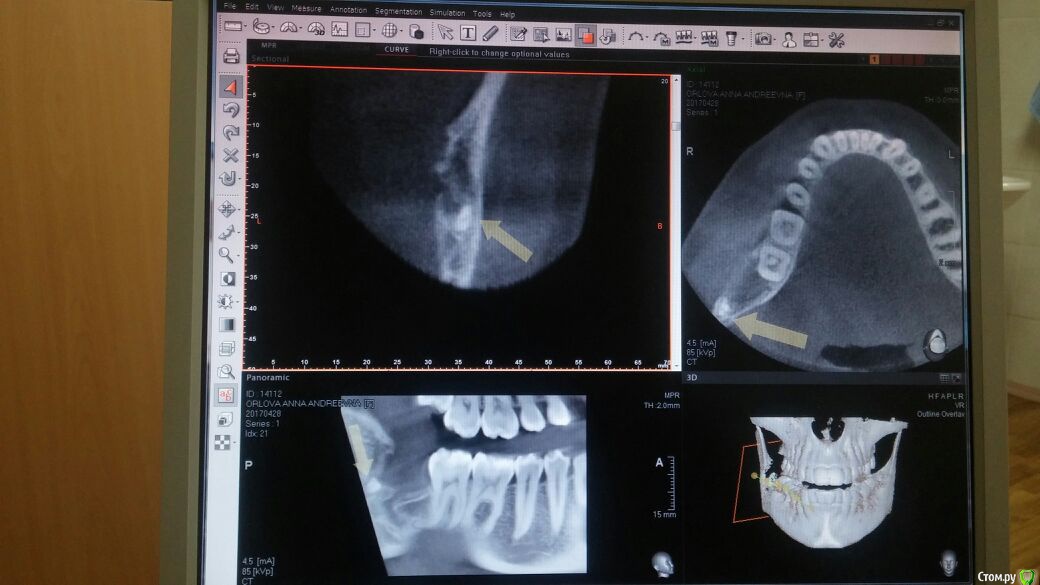

Aristokratka Опубликовано 23 мая, 2017 Поделиться Опубликовано 23 мая, 2017 (изменено) 16.12.16 удаляла правую нижнюю восьмерку.Операция была длительная, чувствительность половины губы и языка до сих пор не появилась.14 дней добросовестно ходила на перевязку и перед новым годом со спокойной душой уехала к родителям из Москвы. в новый год начали беспокоить боли, пришла 16 января к доктору, он прочистил лунку и достал забытый кусочек турунды(((, думала что на этом мои мучения закончились.но лунка не заживает, беспокоит периодически боль и начал появляться неприятных запах, хотя промываю ее постоянно даже сейчас.Перед майскими праздниками зашла в районную стоматологию и хирург меня отправил на КТ, по результатам чего констатировал остаток корня, но удалять отказался, сказал - иди к тому кто удалял зуб.Боюсь идти, прикрепляю снимки. Сильно опять расковыряют??? Изменено 23 мая, 2017 пользователем Aristokratka Ссылка на комментарий

Aristokratka Опубликовано 24 мая, 2017 Автор Поделиться Опубликовано 24 мая, 2017 Да, полгода не заживала. Сегодня удалили корень, крупненький, с половинку горошины наверно, искал доктор его минут 30, нашелся кусок турунды под тканями в добавок ко всему((( надеюсь теперь все заживет. Ссылка на комментарий